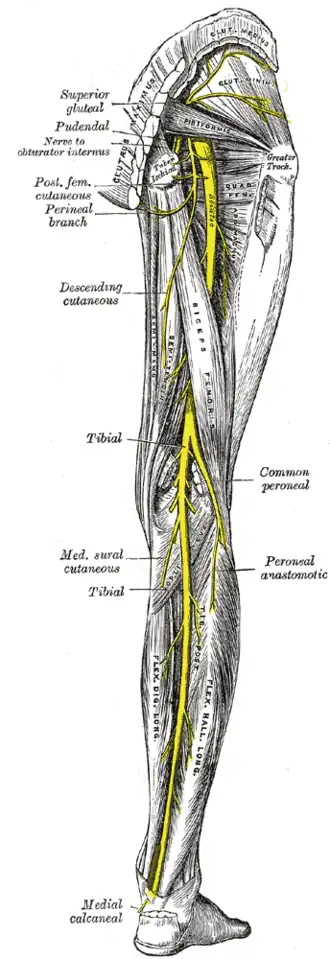

Les artères de la cuisse. Les nerfs su membre inférieur. Vue postérieure Posterior view.

Les nerfs su membre inférieur. Vue postérieure Posterior view. Vue anatomique du dos.